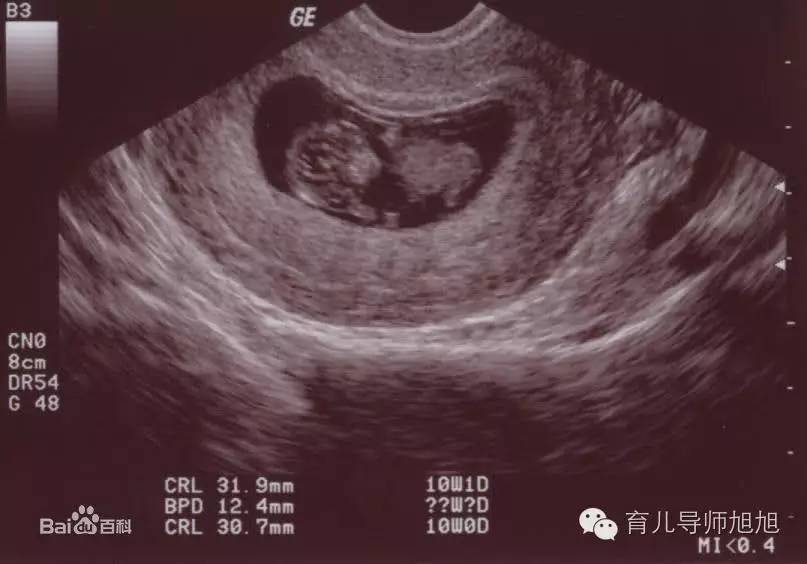

医生告诉何女士,羊水过少,胎儿属于过期妊娠,因为在宫内大便,使得羊水污染严重,并吸入粪便和羊水,现在肺里全是大小不一的胎粪颗粒,导致孩子几乎无法呼吸,若不是及时进行处理,会导致婴儿肺炎、气胸、呼吸衰竭等严重并发症。